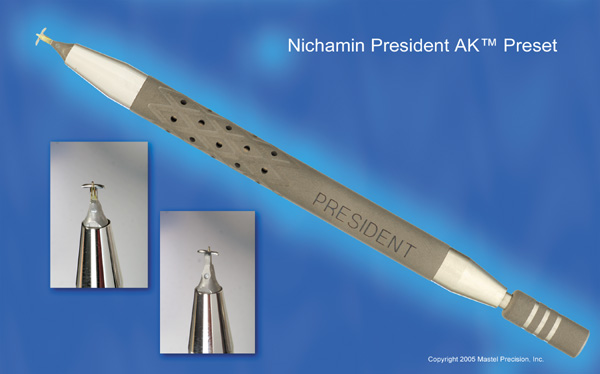

As noted, in the setting of concomitant cataract surgery, an empiric blade

depth setting of 600 microns is commonly employed. Various knives

have been designed specifically for this application, ranging from disposable

steel blades to exquisite gemstone diamond knives. Synthetic (and

less expensive) diamond materials are also available and

are intended for limited reuse. Our preference is for diamond blade technology

that incorporates a single small and arced footplate for enhanced

visualization at the limbus (Mastel Precision). Two models

are available, one with a preset depth of 600 microns and the other

with an adjustable micrometer handle (Fig. 6). Similar designs are available from Rhein Medical, Storz, ASICO, and

other manufacturers.   Fig. 6. (A)A diamond blade with a preset depth of 600 microns is used

to perform LRIs for routine cataract surgery. (B) An adjustable

depth micrometer blade is used in conjunction with the NAPA nomogram

when treating younger patients. Fig. 6. (A)A diamond blade with a preset depth of 600 microns is used

to perform LRIs for routine cataract surgery. (B) An adjustable

depth micrometer blade is used in conjunction with the NAPA nomogram

when treating younger patients.